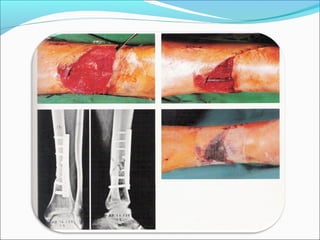

Caso Clínico  Pacientemasculino de 27 anos, golpeado con placa de piedra en pierna izquierda.  Lesión 10X5 cm., en región medial de pierna, con hueso fracciones de hueso visible. LESION GRADO II

Cierre parcial deherida con malla protectora.

Movimiento completo yconsolidación de fractura